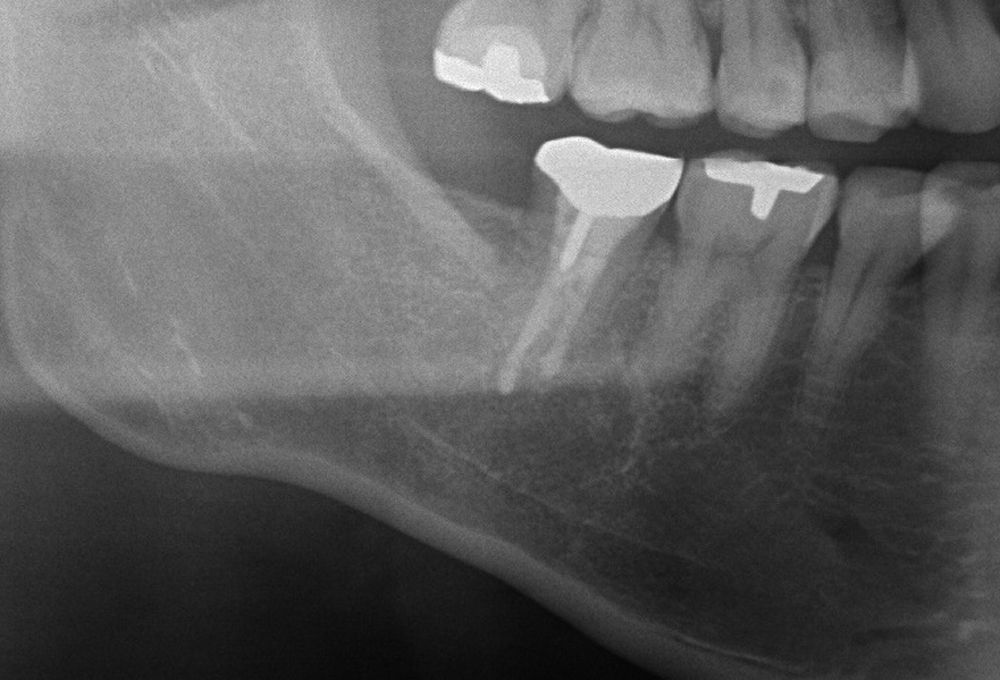

①術前 歯冠大の根尖病変